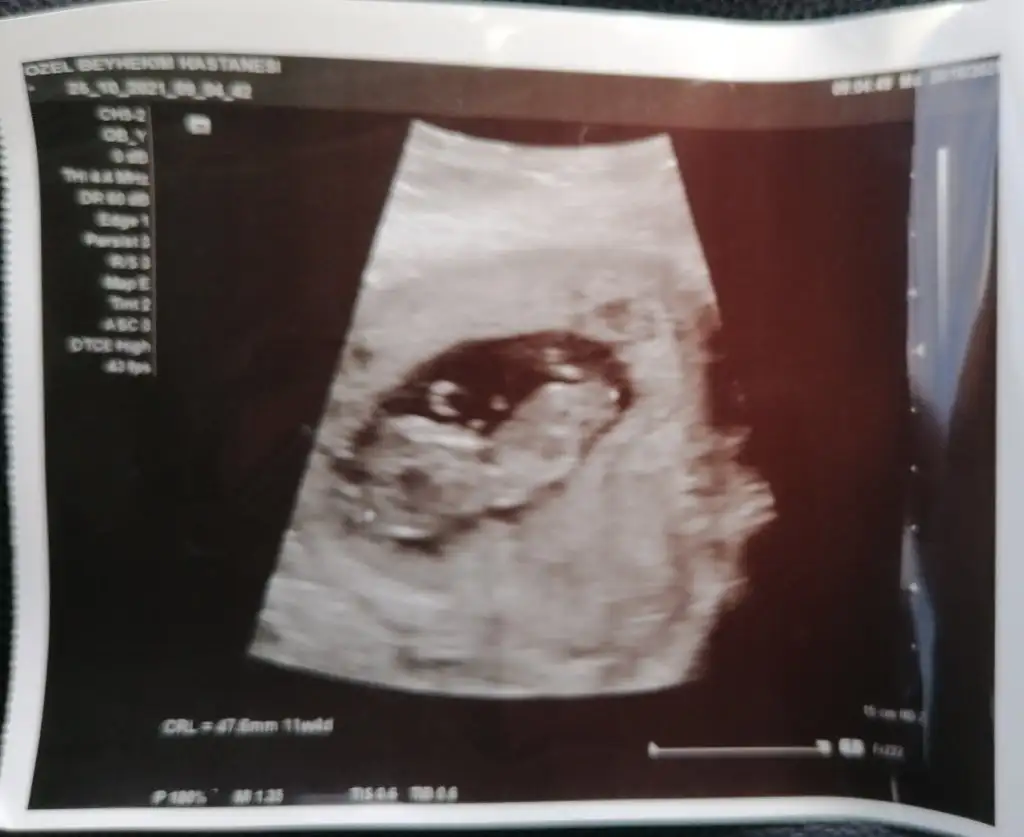

Ultrason cihazı pek kaliteli görüntü vermemiş zaten diğer arkadaşlarımızın ve benim baya netti görüntülerimizGünaydın kızlar bugün 11+3te kontrolüm vardı. Cinsiyet tahmini için erken dedi. Mide bulantım için prilam verdi, vitaminleri yazdı. Haftaya 2li test için çağırdı.

Eki Görüntüle 2939477